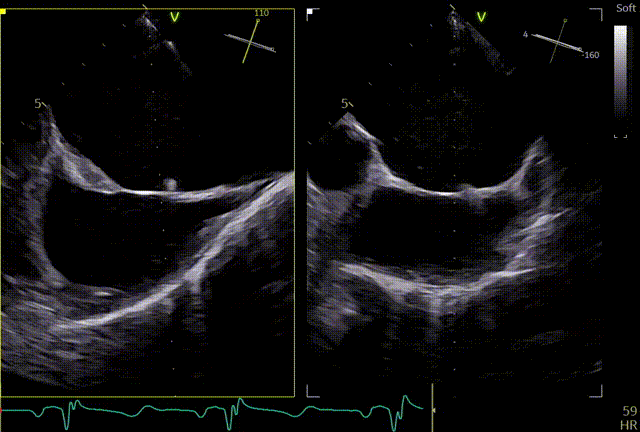

第一个夹子XTW

关小夹子,进入到左室后,跨瓣越过瓣叶尖端后,立马打开夹子,三维再次确认夹臂方向未改变,慢慢往上提拉,一次准确捕获瓣叶,前后叶Bouncing明显,后叶接近根部,关紧夹臂,反流量整体减少,但是内外侧都残余反流,内侧为主。反流明显减少,后叶夹持10mm以上,夹子稳定性良好,跨瓣压差小于3mmHg,决定释放。

释放前评估

释放后

释放后内侧后叶仍旧栓系,反流较重,内外侧都残余反流,内侧为主,考虑到内侧反流较宽,瓣叶够长,栓系难以捕捞,压差不高,第二枚夹子选择XTW,置入第二枚XTW后,在1区上方做轨迹测试,充分释放张力,调整夹子的夹臂方向位于5点-11点的位置,回拉系统,使第二枚夹子位于3区,关小夹子进入到心室侧,由于第一枚夹子起到了稳定瓣叶的作用,第二枚夹子捕捞夹持也异常顺利,一次精准捕获前叶和后叶,再次完整评估二尖瓣夹XTW的方向、组织桥稳定性、瓣叶受限程度及反流减小程度。前后叶Bouncing明显,但是反流却明显增加,开始未明确原因,Orientation,夹持量均无问题,但是内侧还残余反流,考虑内侧可能还要补,决定打开贴近第一个夹子放置,如果有需要内侧再补,此时发现由于患者EF值低,麻醉老师肾上腺素一直在给,心脏搏动较为剧烈,反流术中的异常增多可能是由于此原因导致,遂停止给药。

第二个XTW第一次夹持

第二个XTW第二次夹持